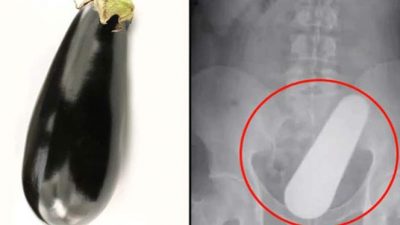

যুবকের পায়ুপথে অপারেশনে বের হলো আস্ত বেগুন!

আকাশবার্তা ডেস্ক : কোষ্ঠকাঠিন্যের যন্ত্রণায় অনেকে সারা বছর ভুগে থাকেন। শৌচাগারে ঘণ্টার পর ঘণ্টা সময় কাটিয়েও তাদের মল পরিষ্কার হয় না। বেশ কিছুদিন ধরে এমন সমস্যায় ভুগছিলেন চীনের এক যুবক। বিস্তারিত...